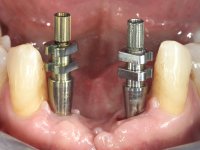

Após estudo imagiológico foi planificada a colocação de dois implantes de 3.3 mm de diâmetro e 10 mm de comprimento. No dia da cirurgia foram extraídos os dentes 42 e 32 e removido o implante. Os implantes foram colocados na zona dos alvéolos tendo o cuidado de lingualizar um pouco o seu posicionamento. Foi feita uma impressão pela técnica de moldeira aberta com o retalho aberto para a confeção da ponte provisória imediata. Enquanto a impressão foi para o laboratório, foram colocados parafusos de cicatrização altos e feita a sutura da ferida cirúrgica. A paciente esperou 2 horas na sala de espera enquanto no laboratório era confecionada a ponte provisória. A ponte provisória imediata aparafusada foi colocada e o seu assentamento controlado imagiologicmente. Passados 3 meses foi realizada a impressão definitiva com uma técnica de moldeira aberta. Nessa consulta aproveitamos para polir a ponte provisória com taças de borracha para que os tecidos moles pudessem maturar em melhores condições. Foi feita a recolha de informação para caracterizar da melhor forma a estrutura monolítica em Zr. Foram utilizadas guias de cor para a cerâmica de tonalidade coronária e gengival. No laboratório foi confecionada uma ponte em Zr. aparafusada que foi cuidadosamente caracterizada. Após aprovação pela paciente foi colocada definitivamente em boca. O aperto foi feito com uma chave dinâmica com 35 N de torque. Os orifícios foram tapados com teflon e obturados com resina composta.